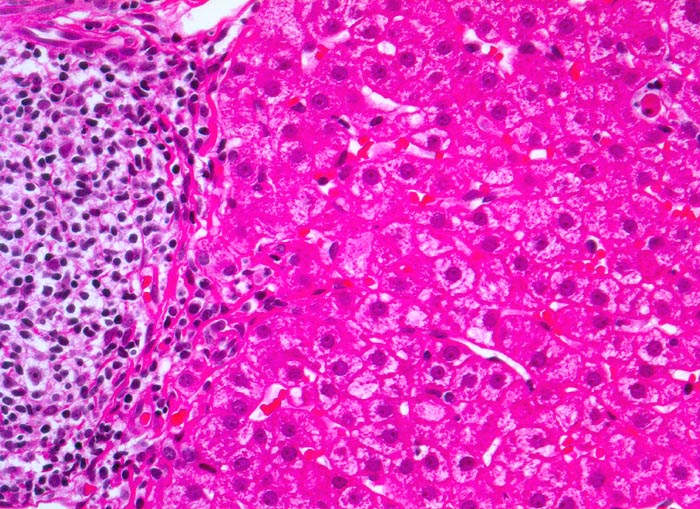

Morphologische Merkmale:

• Dichte mononukleäre portale und lobuläre Entzündungsinfiltrate mit Ausbildung von Lymphfollikeln in den Portalfeldern.

• Übergreifen der Entzündung auf das Parenchym (=Interface oder Grenzzonenhepatitis).

• Abgerundete hypereosinophile apoptotische Hepatozyten (Councilman-Körperchen).

• Geringe Portalfeldfibrose. Das sollte der Kliniker dem Pathologen mitteilen: